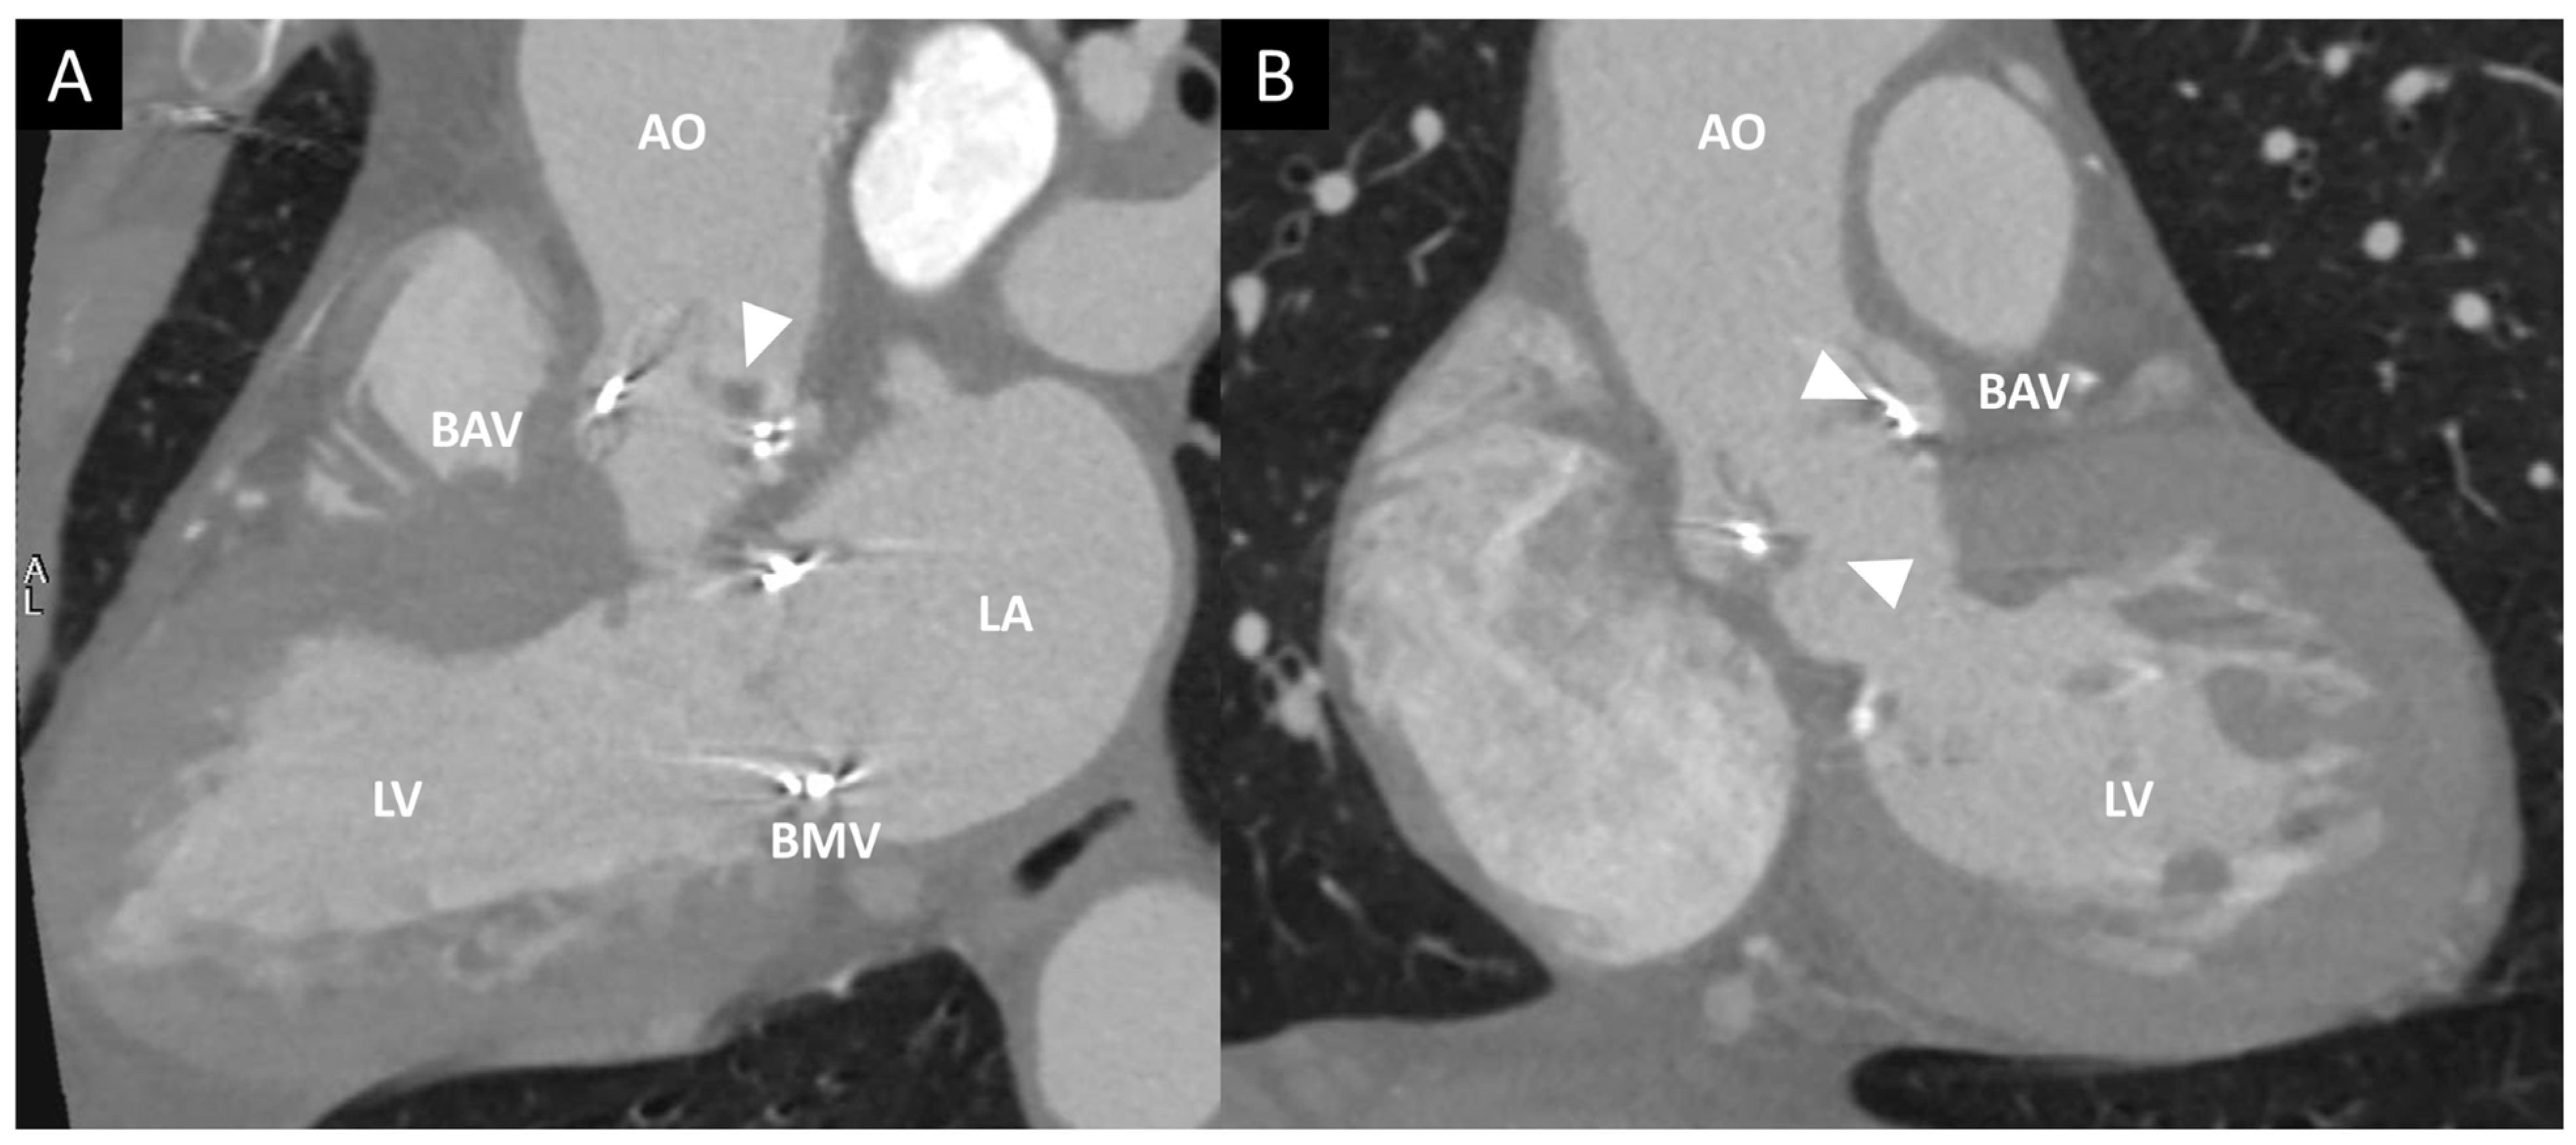

Figure 9. Contrast CT in a patient with endocarditis of a bioprosthetic aortic valve (BAV). (A,B) Multiplanar reconstruction of LV long axis (A) and LV short axis (B). Arrowheads show the presence of hypodense masses adherent to BAV leaflets. AO, aorta; BMV, bioprosthetic mitral valve; LA, left atrium; LV, left ventricle.